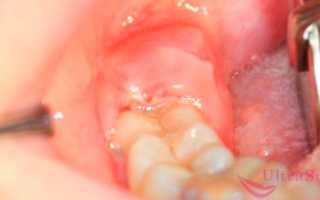

Прорезывающийся зуб мудрости

Почему еще может одновременно болеть голова и челюсть? Если у вас начал резаться зуб мудрости, что обычно происходит во взрослом возрасте, то очень может быть, что именно он стал виновником проблемы. Массивный третий моляр мучительно долго проходит через челюстную кость, задевает нервные окончания, отчего возникает болевой синдром. Однако сказать, где точно болит, очень сложно, потому что ощущения размыты, часто они захватывают челюсть, на которой режется «восьмерка», а также отдают в голову и виски.

Если вы стали обладателем «восьмерки», то обязательно покажитесь стоматологу и сделайте рентген. Очень часто третьи моляры оказываются ретинированными и дистопированными, что приводит к серьезным последствиям для всей полости рта, если их не удалить: они вызывают скученность зубного ряда и патологии прикуса, провоцируют острое гнойное воспаление десневого капюшона (перикоронарит), разрушают соседние единицы, прорезываются уже пораженными кариесом и пульпитом – все это тоже может приводить к болезненным ощущениям в области головы и челюсти.